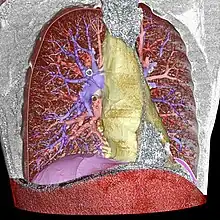

The result of image segmentation is a set of segments that collectively cover the entire image, or a set of contours extracted from the image (see edge detection). Each of the pixels in a region are similar with respect to some characteristic or computed property,[3] such as color, intensity, or texture. Adjacent regions are significantly different color respect to the same characteristic(s).[1] When applied to a stack of images, typical in medical imaging, the resulting contours after image segmentation can be used to create 3D reconstructions with the help of geometry reconstruction algorithms like marching cubes.[4]

– blue: pulmonary arteries

– red: pulmonary veins (and also the abdominal wall)

– yellow: the mediastinum

– violet: the diaphragm

- Medical imaging,[6][7] and imaging studies in biomedical research, including volume rendered images from computed tomography, magnetic resonance imaging, as well as volume electron microscopy techniques such as FIB-SEM.[8]